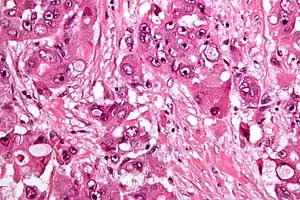

| Micrograph of fibrolamellar hepatocarcinoma showing the characteristic laminated fibrosis between the tumor cells with a low NC ratio. H&E stain. | |

The histopathology of FLC is characterized by laminated fibrous layers, interspersed between the tumor cells. Cytologically, the tumor cells have a low nuclear to cytoplasmic ratio with abundant eosinophilic cytoplasm.[1] Tumors are non-encapsulated, but well circumscribed, when compared to conventional HCC (which typically has an invasive border).